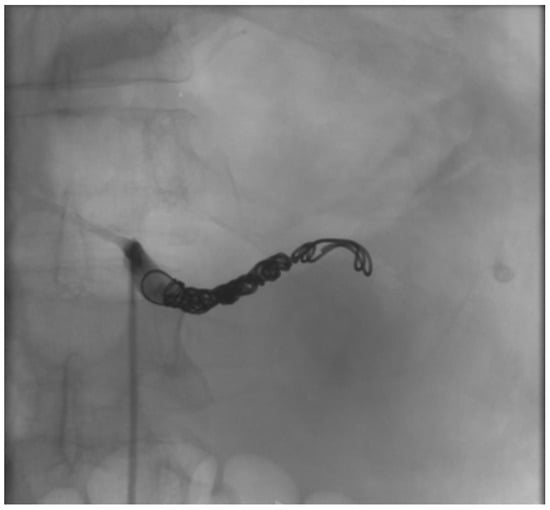

2.1. Case Report